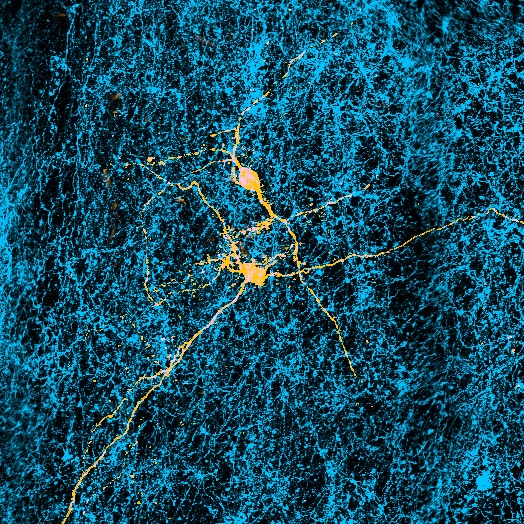

Ma è possibile esporre persone sole a immagini di persone amichevoli che offrono spunti sociali, come un sorriso, e quindi monitorare e registrare i cambiamenti nel flusso sanguigno in diverse parti del cervello utilizzando l’imaging fMRI. E, grazie a precedenti esperimenti, gli scienziati hanno una buona idea di dove cercare nel cervello, un’area analoga a quella che Matthews e Tye hanno studiato sui topi.

Alla fine di ogni sessione, ai soggetti è stato chiesto di salire sullo scanner fMRI e sono stati esposti a immagini diverse: alcune mostravano persone che offrivano segnali sociali non verbali e altre contenevano immagini di cibo. A differenza di Tye e Matthews, Tomova non è stata in grado di individuare i singoli neuroni, ma è stata in grado di monitorare i cambiamenti nel flusso sanguigno all’interno di aree più ampie della scansione, note come voxel, che mostrano l’attività mutevole di popolazioni discrete di diverse migliaia di neuroni. Tomova si è concentrata su aree del mesencefalo note per essere ricche di neuroni associati alla produzione e all’elaborazione del neurotrasmettitore dopamina.

Queste aree sono già state collegate in altri esperimenti alla sensazione di “desiderare” qualcosa. In genere si illuminano in risposta alle immagini del cibo quando una persona ha fame, o a immagini legate alla droga nelle persone con dipendenza. Si è verificato lo stesso comportamento in persone sole quando vengono mostrate loro immagini di un sorriso?

La risposta è stata chiara: dopo l’isolamento sociale, le scansioni cerebrali dei soggetti mostravano molta più attività nel mesencefalo quando venivano mostrate le immagini dei segnali considerati sociali. Quando i soggetti erano affamati, ma non avevano passato un periodo in isolamento, mostravano una reazione altrettanto robusta ai segnali alimentari, ma non a quelli sociali. “Che si tratti della spinta al contatto sociale o della spinta ad altre cose come il cibo, il tipo di rappresentazione sembra essere molto simile”, afferma Tomova.